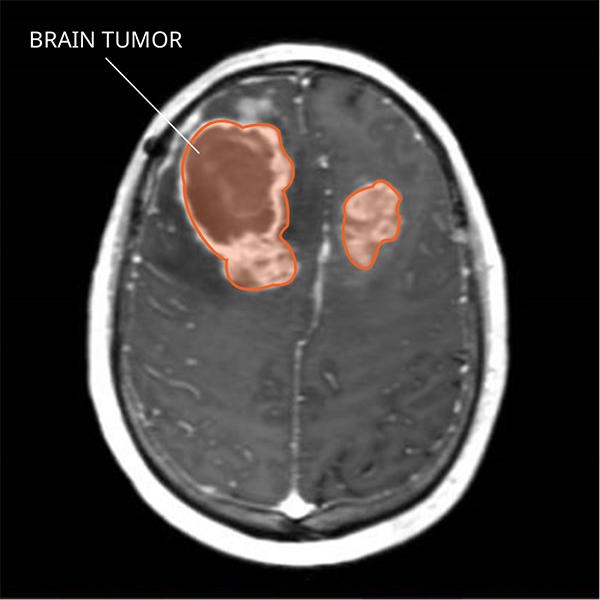

What Do Gliosarcomas Look like on an MRI?

Gliosarcomas usually appear as a single tumor with vague borders. The tumors may occur near the surface of the brain and be attached to the covering of the brain. The tumor often brightens with contrast on a magnetic resonance imaging (MRI) scan. Many tumors can occur in different areas of the CNS. They usually have some swelling around them.